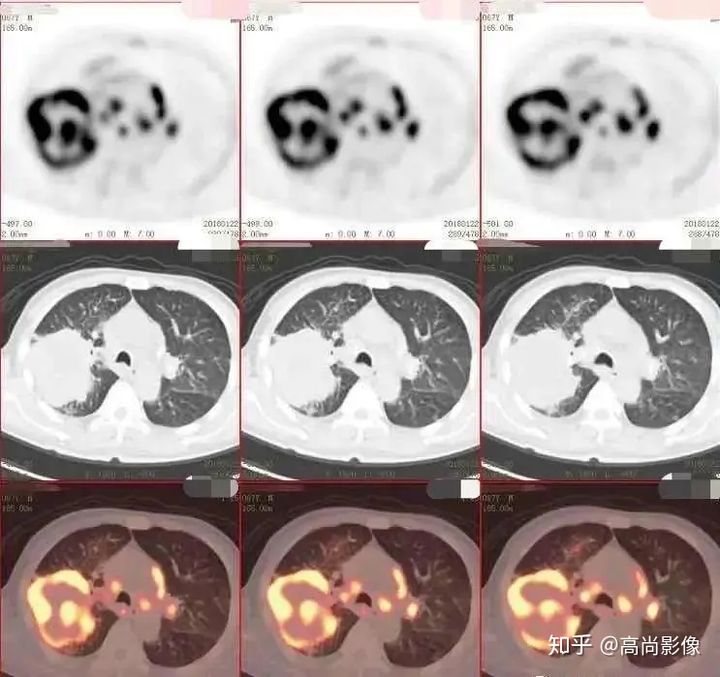

(右肺上葉中央型肺癌)

方大爺?shù)腜ET/CT結(jié)果強烈提示肺癌伴全身多發(fā)轉(zhuǎn)移,已經(jīng)失去手術(shù)機(jī)會,但仍有繼續(xù)化療的機(jī)會。